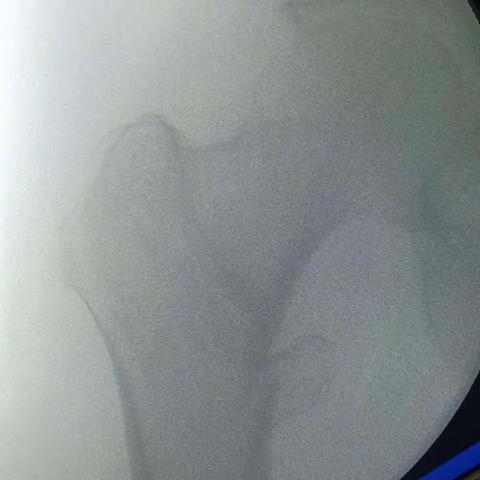

髋关节脱位

2019-08-15 26阅读